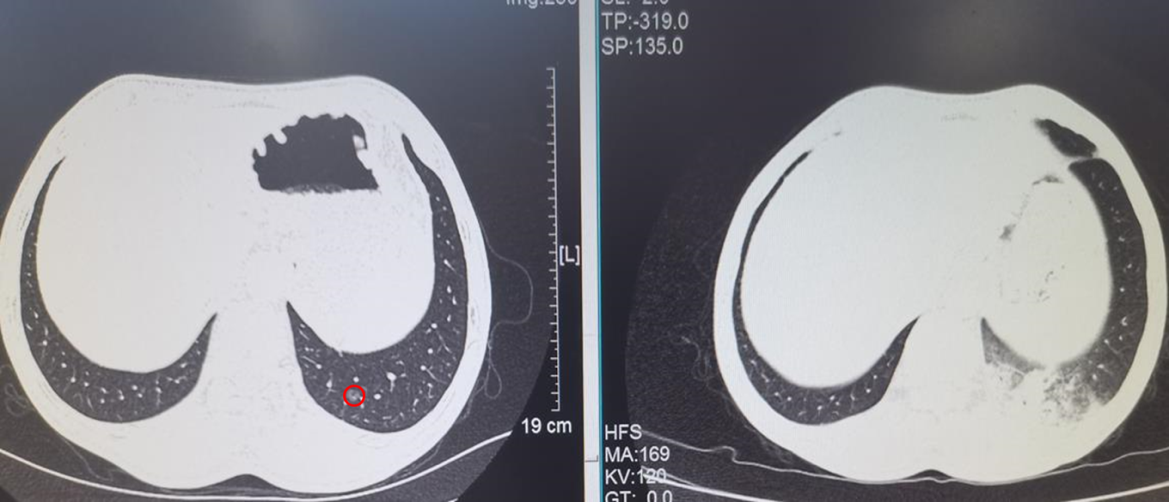

ENB-MWA患者术前小结节位置及消融术后3天复查CT见病灶区域成消融后炎性改变(完全覆盖结节位置)。